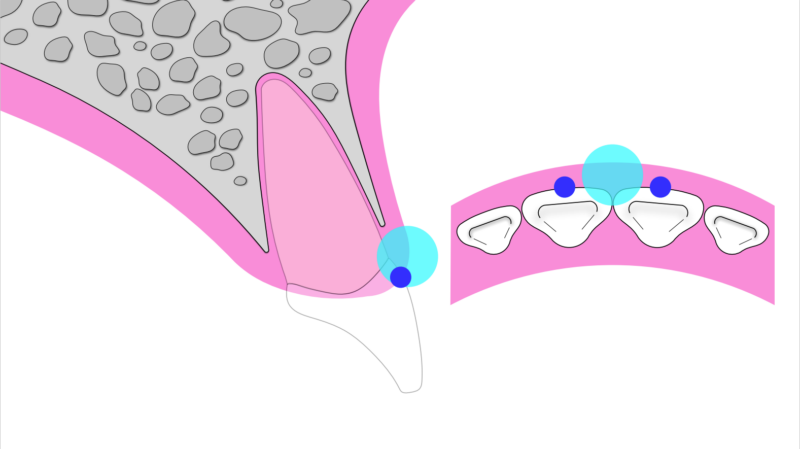

そこで近年注目されているのが、「抜歯と同時にインプラントを入れる方法」です。さらに、歯の一部をあえて残すことで歯肉や骨の形を維持する「ソケットシールドテクニック(SST)」という手法もあります。これにより、組織の吸収を最小限に抑え、より自然な仕上がりが期待できます。

①向かってる左のすぐにインプラントが可能な部分にはSSTを併用し、できるだけ負担の少ない治療を選択。